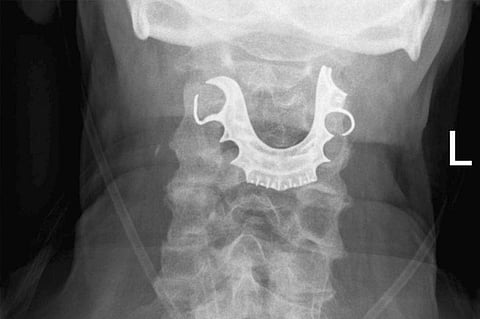

طقم أسنانه الجزئي المكون من صفيحة السقف المعدنية وثلاث أسنان صناعية.. كل ذلك كان عالقًا في الجزء العلوي من الحلق منذ ثمانية أيام مضت، بعد أن أجرى عملية جراحية بسيطة في أحد المستشفيات. وكان الرجل قد اعتقد أنه فقد طقم أسنانه أثناء وجوده في المستشفى لإجراء العملية، حتى أظهرت الأشعة السينية هذه المفاجأة. وحسب الخبراء فإن كيفية حدوث هذا الأمر لا تبدو واضحة تمامًا، وإن تم توثيق ما يقرب من ستة حوادث مماثلة قبل ذلك، وفيها ضلت أطقم الأسنان طريقها في فم المرضى أثناء الجراحة والتخدير.

نشرت المجلة الطبية الأمريكية حالة فريدة أثارت كثيرًا من الجدل مؤخرًا، لبريطاني يبلغ من العمر 72 عامًا، اتجه إلى الطوارئ بأحد المستشفيات وهو يعاني من سعال دموي مع صعوبة في البلع، وعندما كشف عليه الأطباء لم يستطيعوا تحديد سبب ذلك، فأخضعوه للأشعة السينية على الصدر، وبعدها شخصوا حالته بالالتهاب الرئوي، وأعادوه إلى المنزل مع المضادات الحيوية والمسكنات، لكن آلام الرجل ومتاعبه استمرت ولم تتوقف، فأجرى زيارة أخرى إلى المستشفى. وهنا اكتشفت الأشعة السينية المشكلة، التي ظهرت في صورة الأشعة أخيرًا.